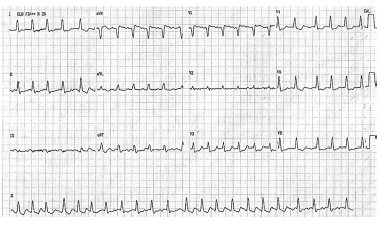

Considere hipoteticamente que paciente do sexo feminino, de 45 anos de idade, chegou ao pronto-socorro com PA de 70 mmHg x 40 mmHg, confusão mental e dispneia. Familiar informa que ela reclamava de sensação de batimentos acelerados e descompassados no coração há seis horas. Ele ainda informa que paciente já apresentou outras vezes episódios de palpitação. Além disso, a enferma tinha sintomas como sudorese, perda de peso, cansaço e dificuldade em dormir há três meses. Paciente não tem histórico de doenças vasculares conhecidas. Posteriormente, foi realizado o ECG.

A respeito desse caso clínico, julgue os itens a seguir.

Deve-se compreender que o que ocasionou a arritmia cardíaca pode ser doença de Graves.